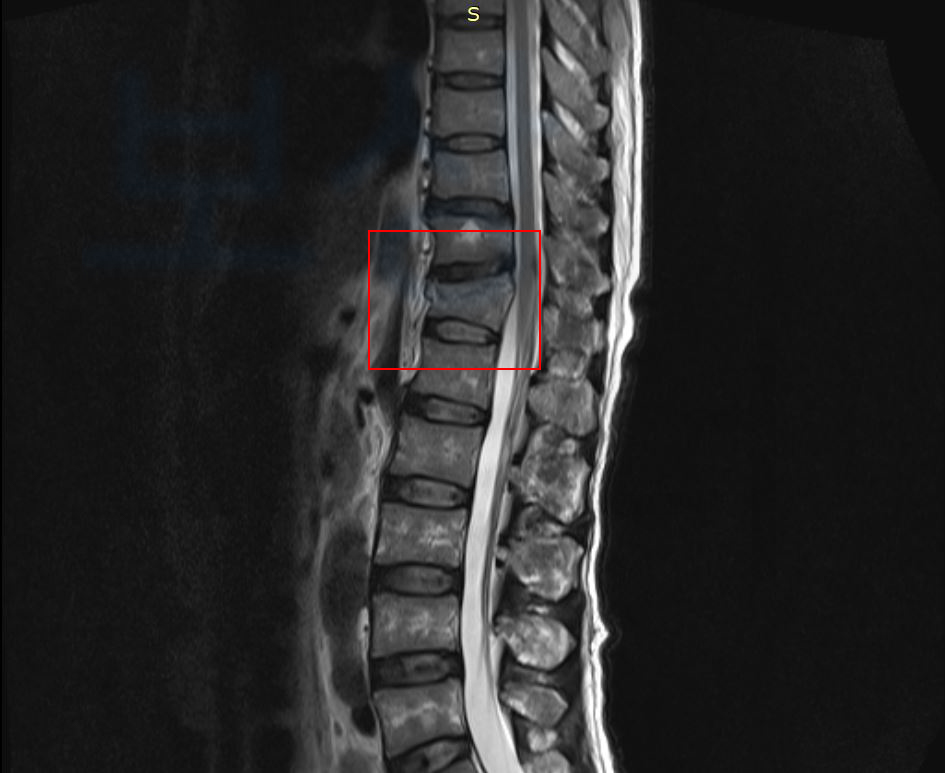

보상파트너로 문의해셨던 교통사고 당해 흉추12번 허리뼈 골절된 임@@님 또한

mri 촬영하니 허리뼈 골절 진단을 받게 되었고 약 약 4주간의 안정을 취해야 했습니다.